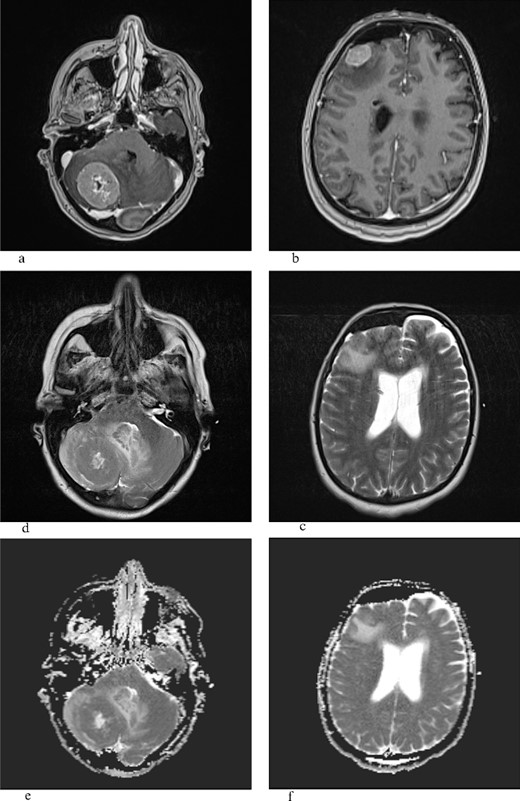

The histopathological findings correspond to fragments of tumor tissue composed of solid clusters of atypical, polygonal epithelial cells displaying visible mucin production in some cells [periodic acid-schiff staining (PAS)-Alcian +]. Immunohistochemically, the tumor cells show positivity for CKAE1/AE3, CK 7, and Gata3 with weak intensity, partially p63 positive, while negative for ER, PR, HER2, TTF-1, CK5/6, p40, CK20, Pax8, Napsin A, CD10, AR, mammaglobin, and CKHMW (Fig. 2).

(a–c) HE, hematoxylin–eosin, PAS Alcian is a histochemical method used to demonstrate mucin production in the tumor; (d, e) CK7 and CKAE1/AE3 are antibodies for cytokeratins-intermediate filaments, parts of the cytoskeleton of epithelial cells, and (f) Gata 3 is usually positive in breast carcinomas but also in salivary gland carcinomas.

Furthermore, the histopathological report confirmed the poorly differentiated mucoepidermoid carcinoma nature of the brain metastases, consistent with a variant of salivary gland-type tumors originating in the lungs with a high squamous epithelial cell which is a prerogative of high-grade MEC [4, 5]. Immunohistochemical analysis further supported the diagnosis, emphasizing the importance of utilizing specific markers such as CKAE1/AE3, CK 7, and Gata3 to distinguish MEC from other malignancies [3]. The negative staining for hormone receptors (ER, PR, and HER2), thyroid transcription factor-1 (TTF-1), and other markers ruled out alternative primary sources [9]. While HER2 expression was reported in high-grade MEC, here we found it to be negative [15] (Fig. 2).